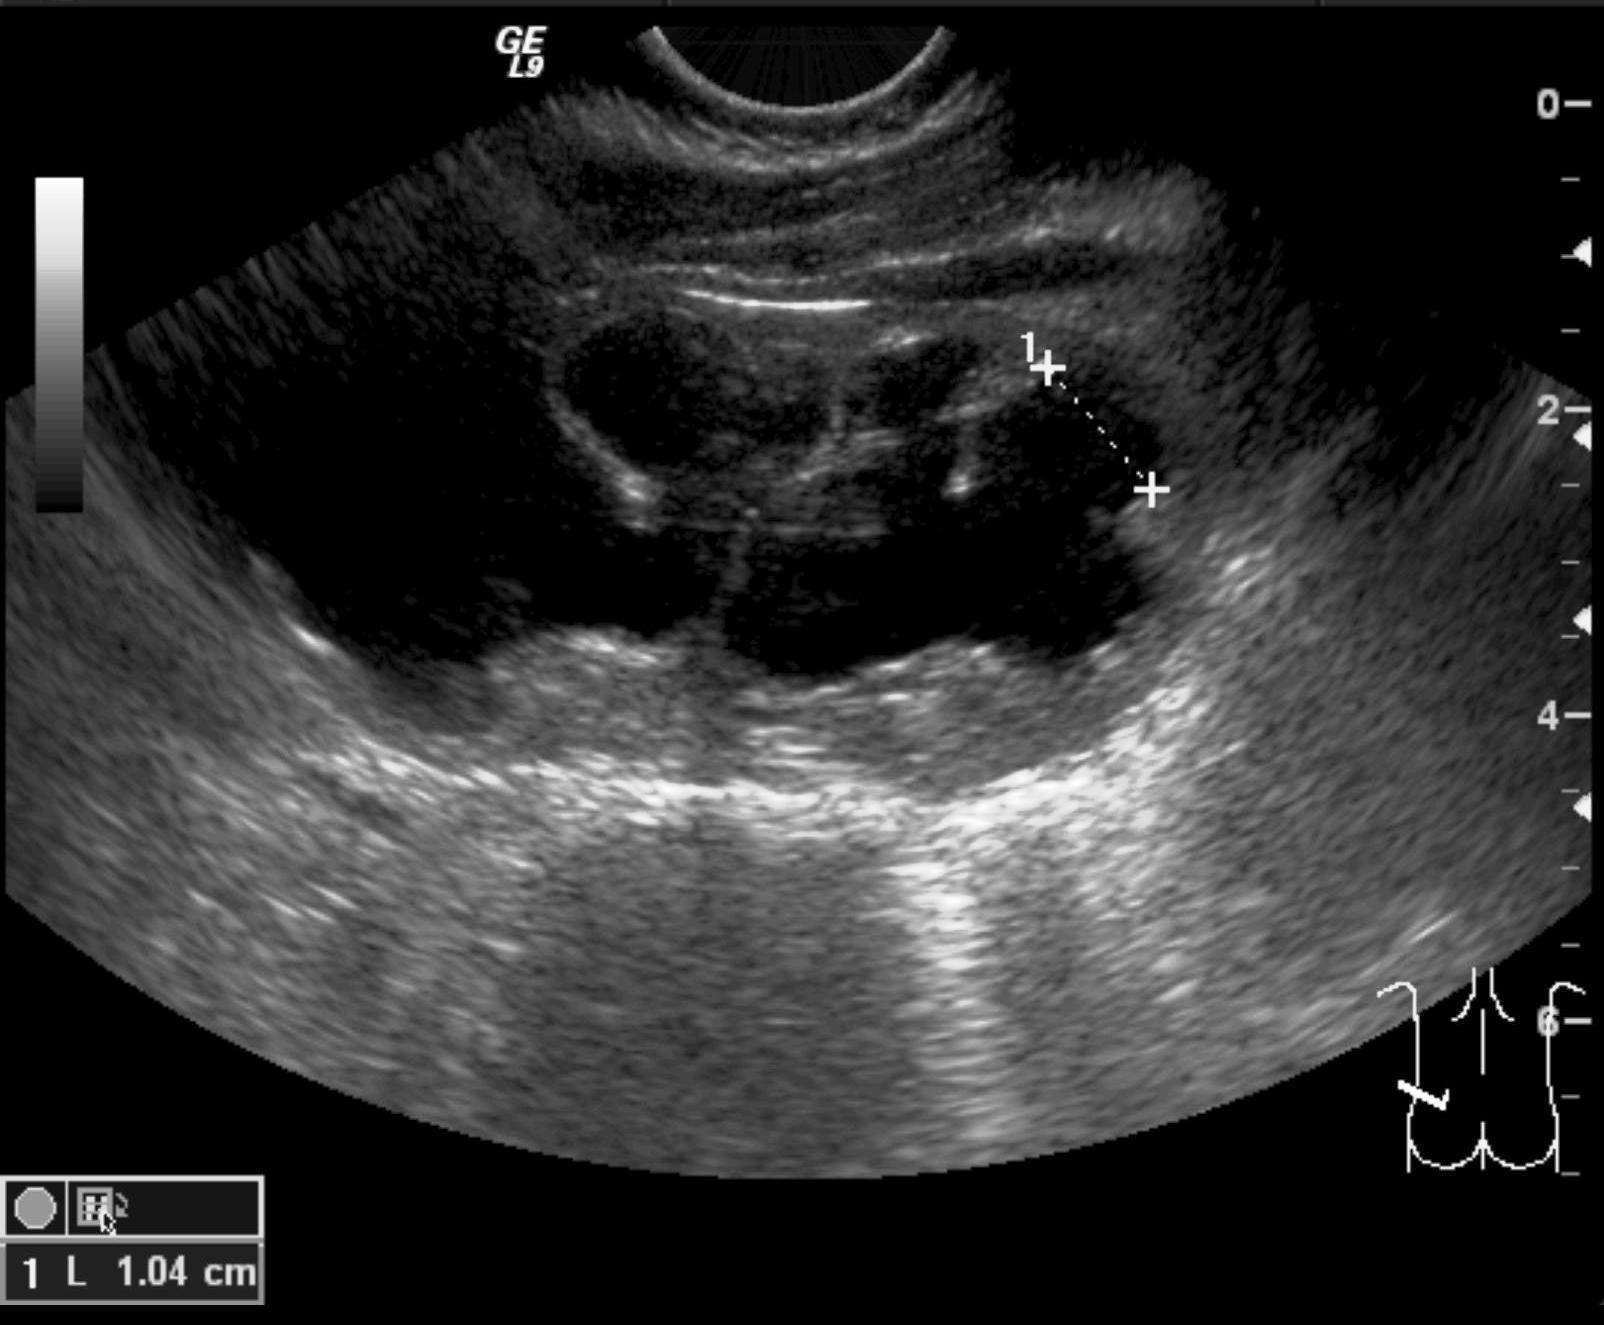

Invagination. A distal intestinal loop invaginating to a proximal intestinal loop can result in a mechanical intestinal obstruction, and cause ischemic damage. It most frequently occurs in infants (3-24 months) with recurring, colic-like complaints, distended intestines, a palpable mass and with frequent vomiting and bloody stool. Invagination requires immediate diagnosis and desinvagination. US exam reveals the invaginated intestines as a “target” sign in axial cross section and looks like a “pseudokidney” in longitudinal cross section. The therapy is hydrostatic or pneumatic desinvagination. Perforation and/or peritonitis are absolute contraindications to these procedures. Hydrostatic desinvagination can be performed under fluoroscopy or with US guidance and is considered successful if air or the contrast material appears in the terminal ileum and the invaginated loop disappears. If these efforts do not succeed, surgical desinvagination is needed.

17. “Target” sign. Invagination. .